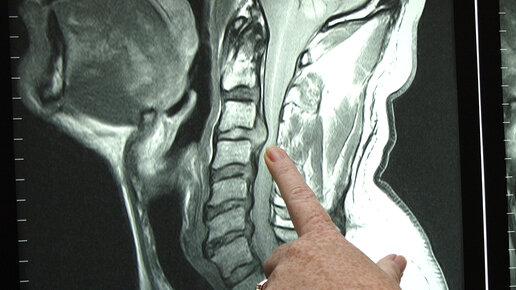

МРТ шейного отдела позвоночника: что показывает и как проходит исследование

МРТ шейного отдела позвоночника – высокоэффективный инструмент обследования, который на сегодняшний день представляет собой один из наиболее информативных способов исследования изменений в спинном мозге и межпозвоночных дисках. Данный вид диагностики позволяет с максимальной точностью выявить повреждения, заболевания и изменения в зоне позвоночного столба и окружающих его мягких тканей. При проведении диагностики на томографе не применяется вредное для человека рентгеновское излучение, поэтому сканирование...